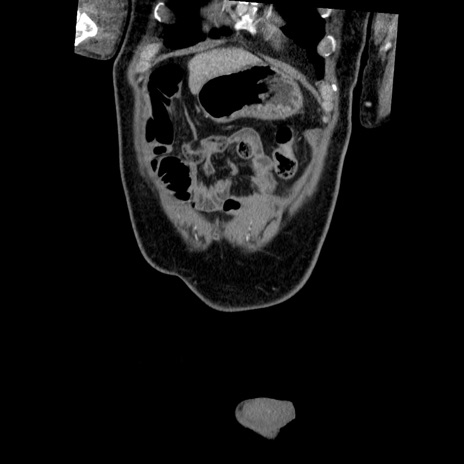

横断像

【症例】50歳代男性

【主訴】腹痛

【現病歴】AVMからの被殻出血のため回復期リハ病棟入院中。 本日午後3時頃急に下腹部痛が出現した。

【既往歴】AVM、被殻出血、虫垂炎、高血圧

【身体所見】意識晴明、左半身不全麻痺、会話の理解は良好、36.5°C、腹部:膨隆、全体に板状硬、下腹部正中に圧痛点あり、反跳痛-、筋性防御不明、右下腹部にope scar

【データ】WBC 9400、CRP 0.06